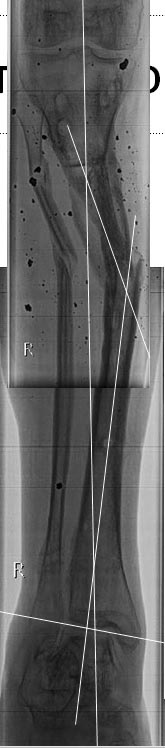

[Ortho] Деформации после минно-взрывного ранения.

правая голень.